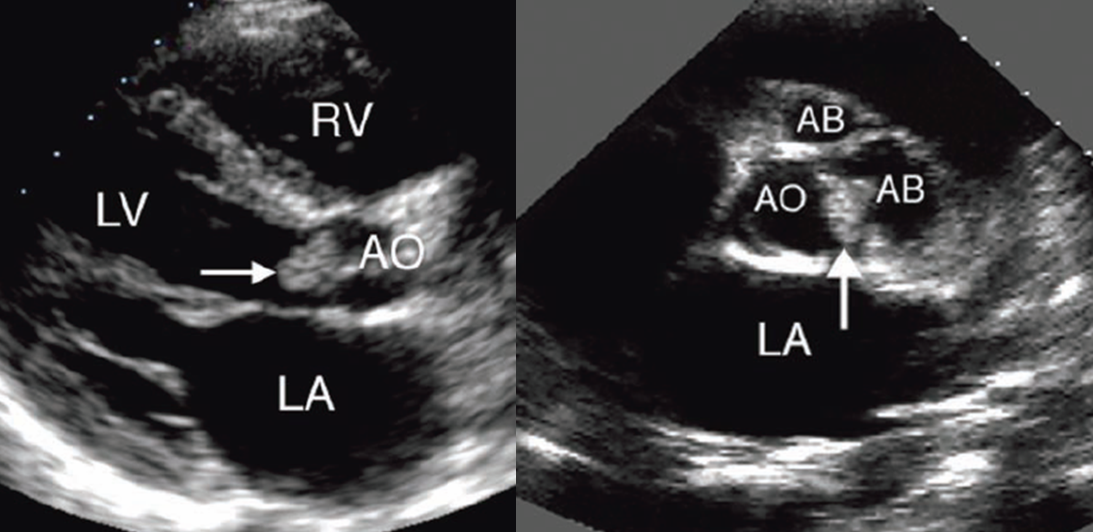

vegetations are more common on sides where

valves are exposed to high velocity regurgitant jets

LV side of AV

LA side of MV

what do IE vegetations look like?

irregularly shaped, low reflective structures that may be sessile (attached at base) or pedunculated